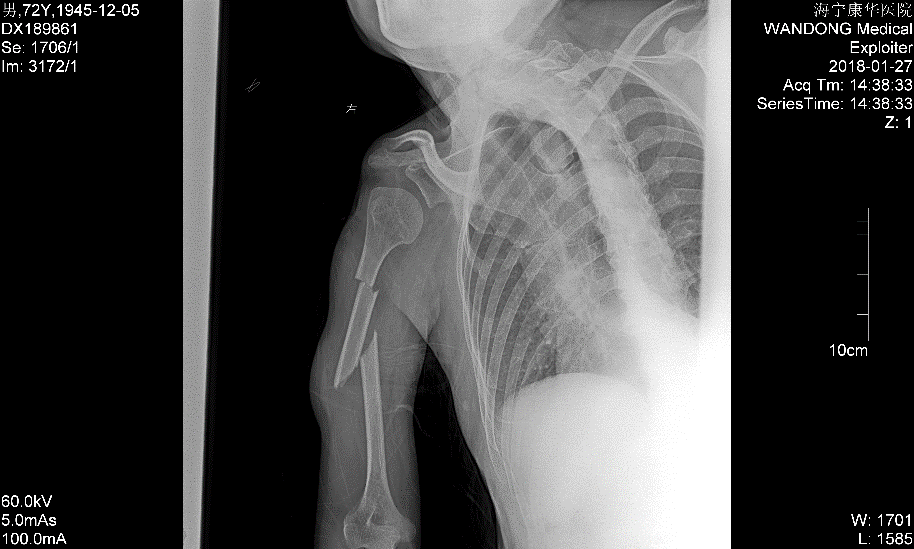

“片子上看属于右肱骨多段骨折,也就是这里和这里,两个地方都骨折了”,陈主任细致地解释着,“一般应该行切开内固定手术,但多段骨折手术皮肤切口较长,剥离广,血供破坏多,骨头愈合也困难。由于大伯右手臂本身有小儿麻痹症,上肢较正常略细,考虑再三,建议试行手法复位夹板外固定治疗,经过与患者及家属的沟通,其欣然接受保守治疗,能不开刀最好。”

“根据大伯的状况,保守治疗的话,可以试试杉树皮外固定,但是这个固定时间会比较长,而且大伯现在是多段骨折,期间移位风险会比较高。”陈主任解释道。

“先试试吧,实在没办法再考虑手术。”李大伯跟儿子达成一致,陈主任便做了手法复位杉树皮外固定的治疗。

“一星期以后再来拍片复查,根据情况要进行位置调整”,陈杰叮嘱过李大伯后再次提醒李先生,并列出不少注意事项,生怕李大伯的手臂再出状况。

一周后,X片显示骨折位置同前,并没有出现移位情况,李先生跟李大伯都面露喜色,陈主任也略略松了口气,又重新为李大伯的外固定进行了调整加固。